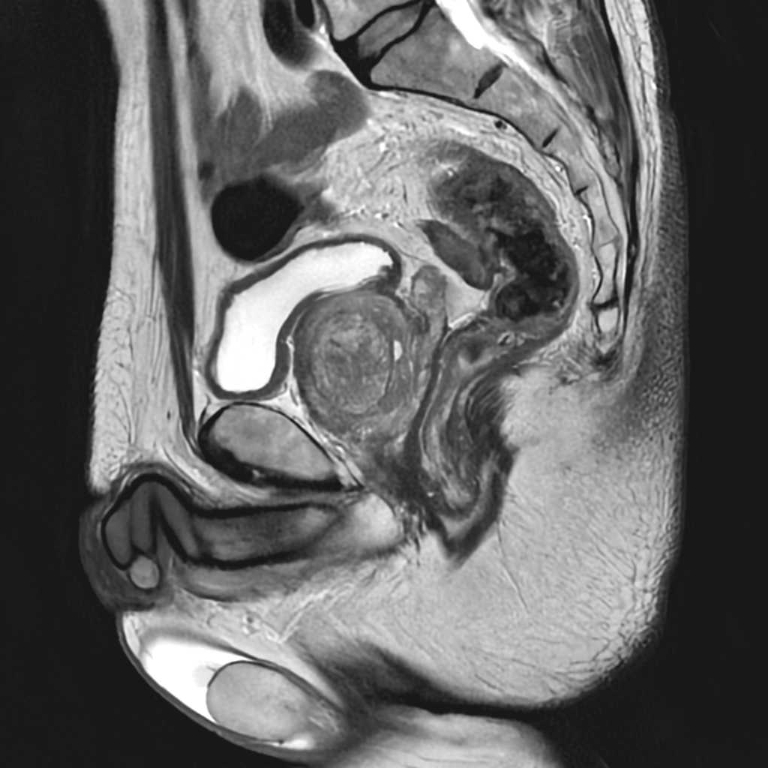

MRI検査

婦人科領域

子宮卵巣

子宮筋腫

卵巣嚢腫